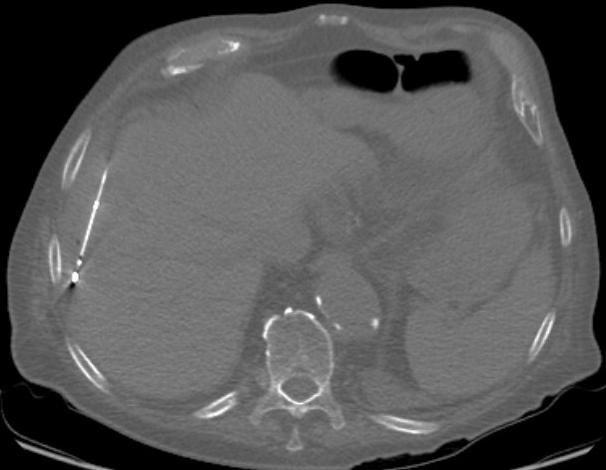

Fotos: 83jähriger Patient mit Hemikolektomie links wegen eines Adenokarzinoms der linken Kolonflexur. Nach einem Jahr Auftreten einer solitären Lebermetastase. Tumorboardbeschluss einer CT-gesteuerten Mikrowellenablation der Lebermetastase.